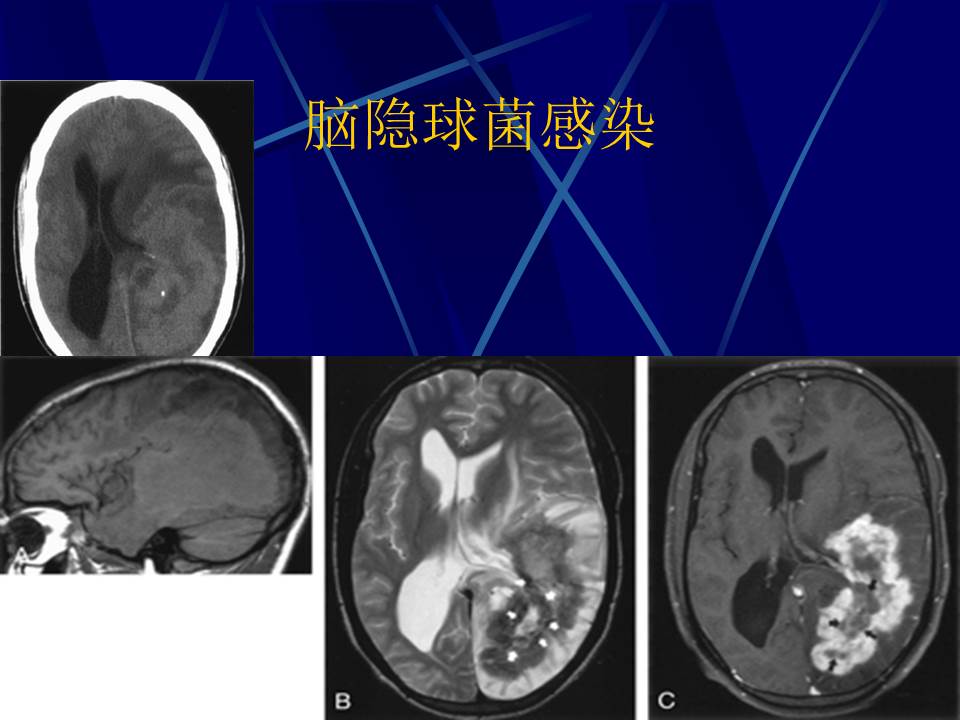

肺部真菌感染影像学分析